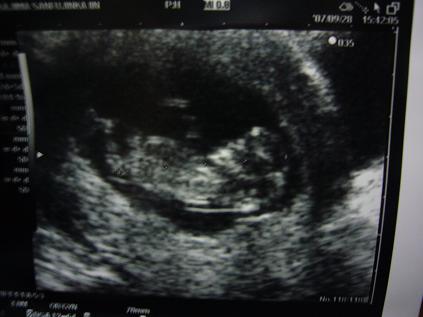

今日は病院へ行ってきました

精密検査で、異常がないか調べる日でした

まったく異常なしでした

そして、ちゃんと人の形になってる!と

最初は豆粒みたいだったんですよねぇ

なんか花の時もだけど、こうなると感動しますねぇ

それも

ああ、動いてるっ!って

そんなに激しくじゃないけどぴょこんぴょこんってちょっとピクンってなるじゃないですか

あれが嬉しくってたまりませんでした

そこでわかった新事実・・・・・

ええ・・・・出産予定日が確実に決まったんですが

4月5日が4月17日になりました・・・・・

なんですか・・・このズレは

1日~5日ぐらいのズレは勘弁しましょう

でも12日もズレるっていったい・・・・・

まあこれで確実に4月の子になりました

花の時みたいに14日ずれても4月の3日・・・・

ですよねぇ(汗

まあ、元気に産まれて来ればよしとしますか

後は性別だけ!

男か女か・・・・わかるのは当分後だそうです